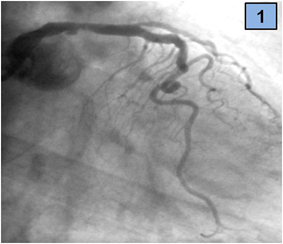

We present a 45-year-old man that was admitted to an emergency department with a history of sudden-onset, severe central chest pain associated with nausea and dyspnoea. Regarding cardiovascular risk factors, he was an active smoker (20 daily cigarettes) and had dyslipidaemia. On hospital arrival, he was lucid and oriented, had normal heart sounds and fine right basal inspiratory lung rales; arterial blood pressure was 120/70 mm Hg and heart rate 76 beats/min. The electrocardiogram showed sinus rhythm with ST segment elevation (4 mm in leads I and aVL, 2 mm in lead aVR), so emergent coronary angiography was indicated. The coronary angiogram showed an image suggestive of rupture plaque, that was located in the distal segment of the LMCA (Figure 1). There were also other lesions, a thrombotic total occlusion of the proximal circumflex (CX) artery and a severe stenosis of the proximal left anterior descending (LAD) artery (Figures 2 & 3). Right coronary artery was dominant with no lesions.

Figure 1 Severe distal LM and ostial LAD lesions with thrombotic occlusion of CX artery, AP view.